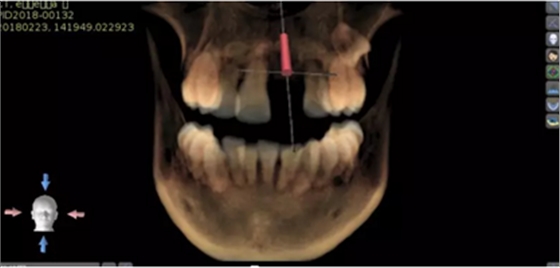

2.術(shù)前植體設(shè)計(jì)

3.術(shù)前導(dǎo)板設(shè)計(jì)

術(shù)后CT